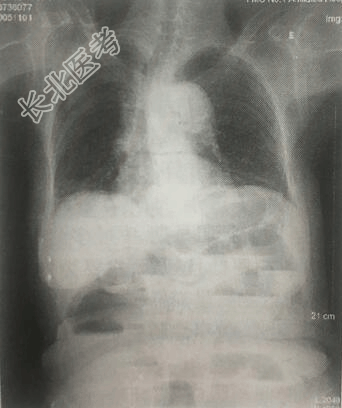

- 单项选择题患者男,22岁。饱餐后活动,突然腹部持续性绞痛,入院后腹部平片如图所示,该患者最有可能出现

E、肠梗阻